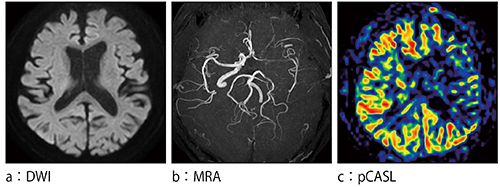

さらに,VISTA法の画像についても高橋医長は,「Prodiva 1.5T CXでは,VISTA法で3D-STIR画像が高画質で撮像できるようになりました。頭頸部領域や脊椎領域の撮像に用いており,SNRの良いきれいな画像を描出できています」と評価している。加えて,頭頸部領域では,Prodiva 1.5T CXに更新したことでpCASL法が使用できるようになり,1.5TにもかかわらずSNRの高いパーフュージョン画像が得られるようになった。頭頸部以外の領域では,4D PCAによる心臓や大血管の血流動態の観察を行っている。高橋医長は,「4D PCAは,データ量も多く撮像時間も要することから,従来はIngenia 3.0Tで使用していましたが,Prodiva 1.5T CXでも,十分臨床で使用できる画像が得られています」と解説する。

症例4:左内頸動脈狭窄